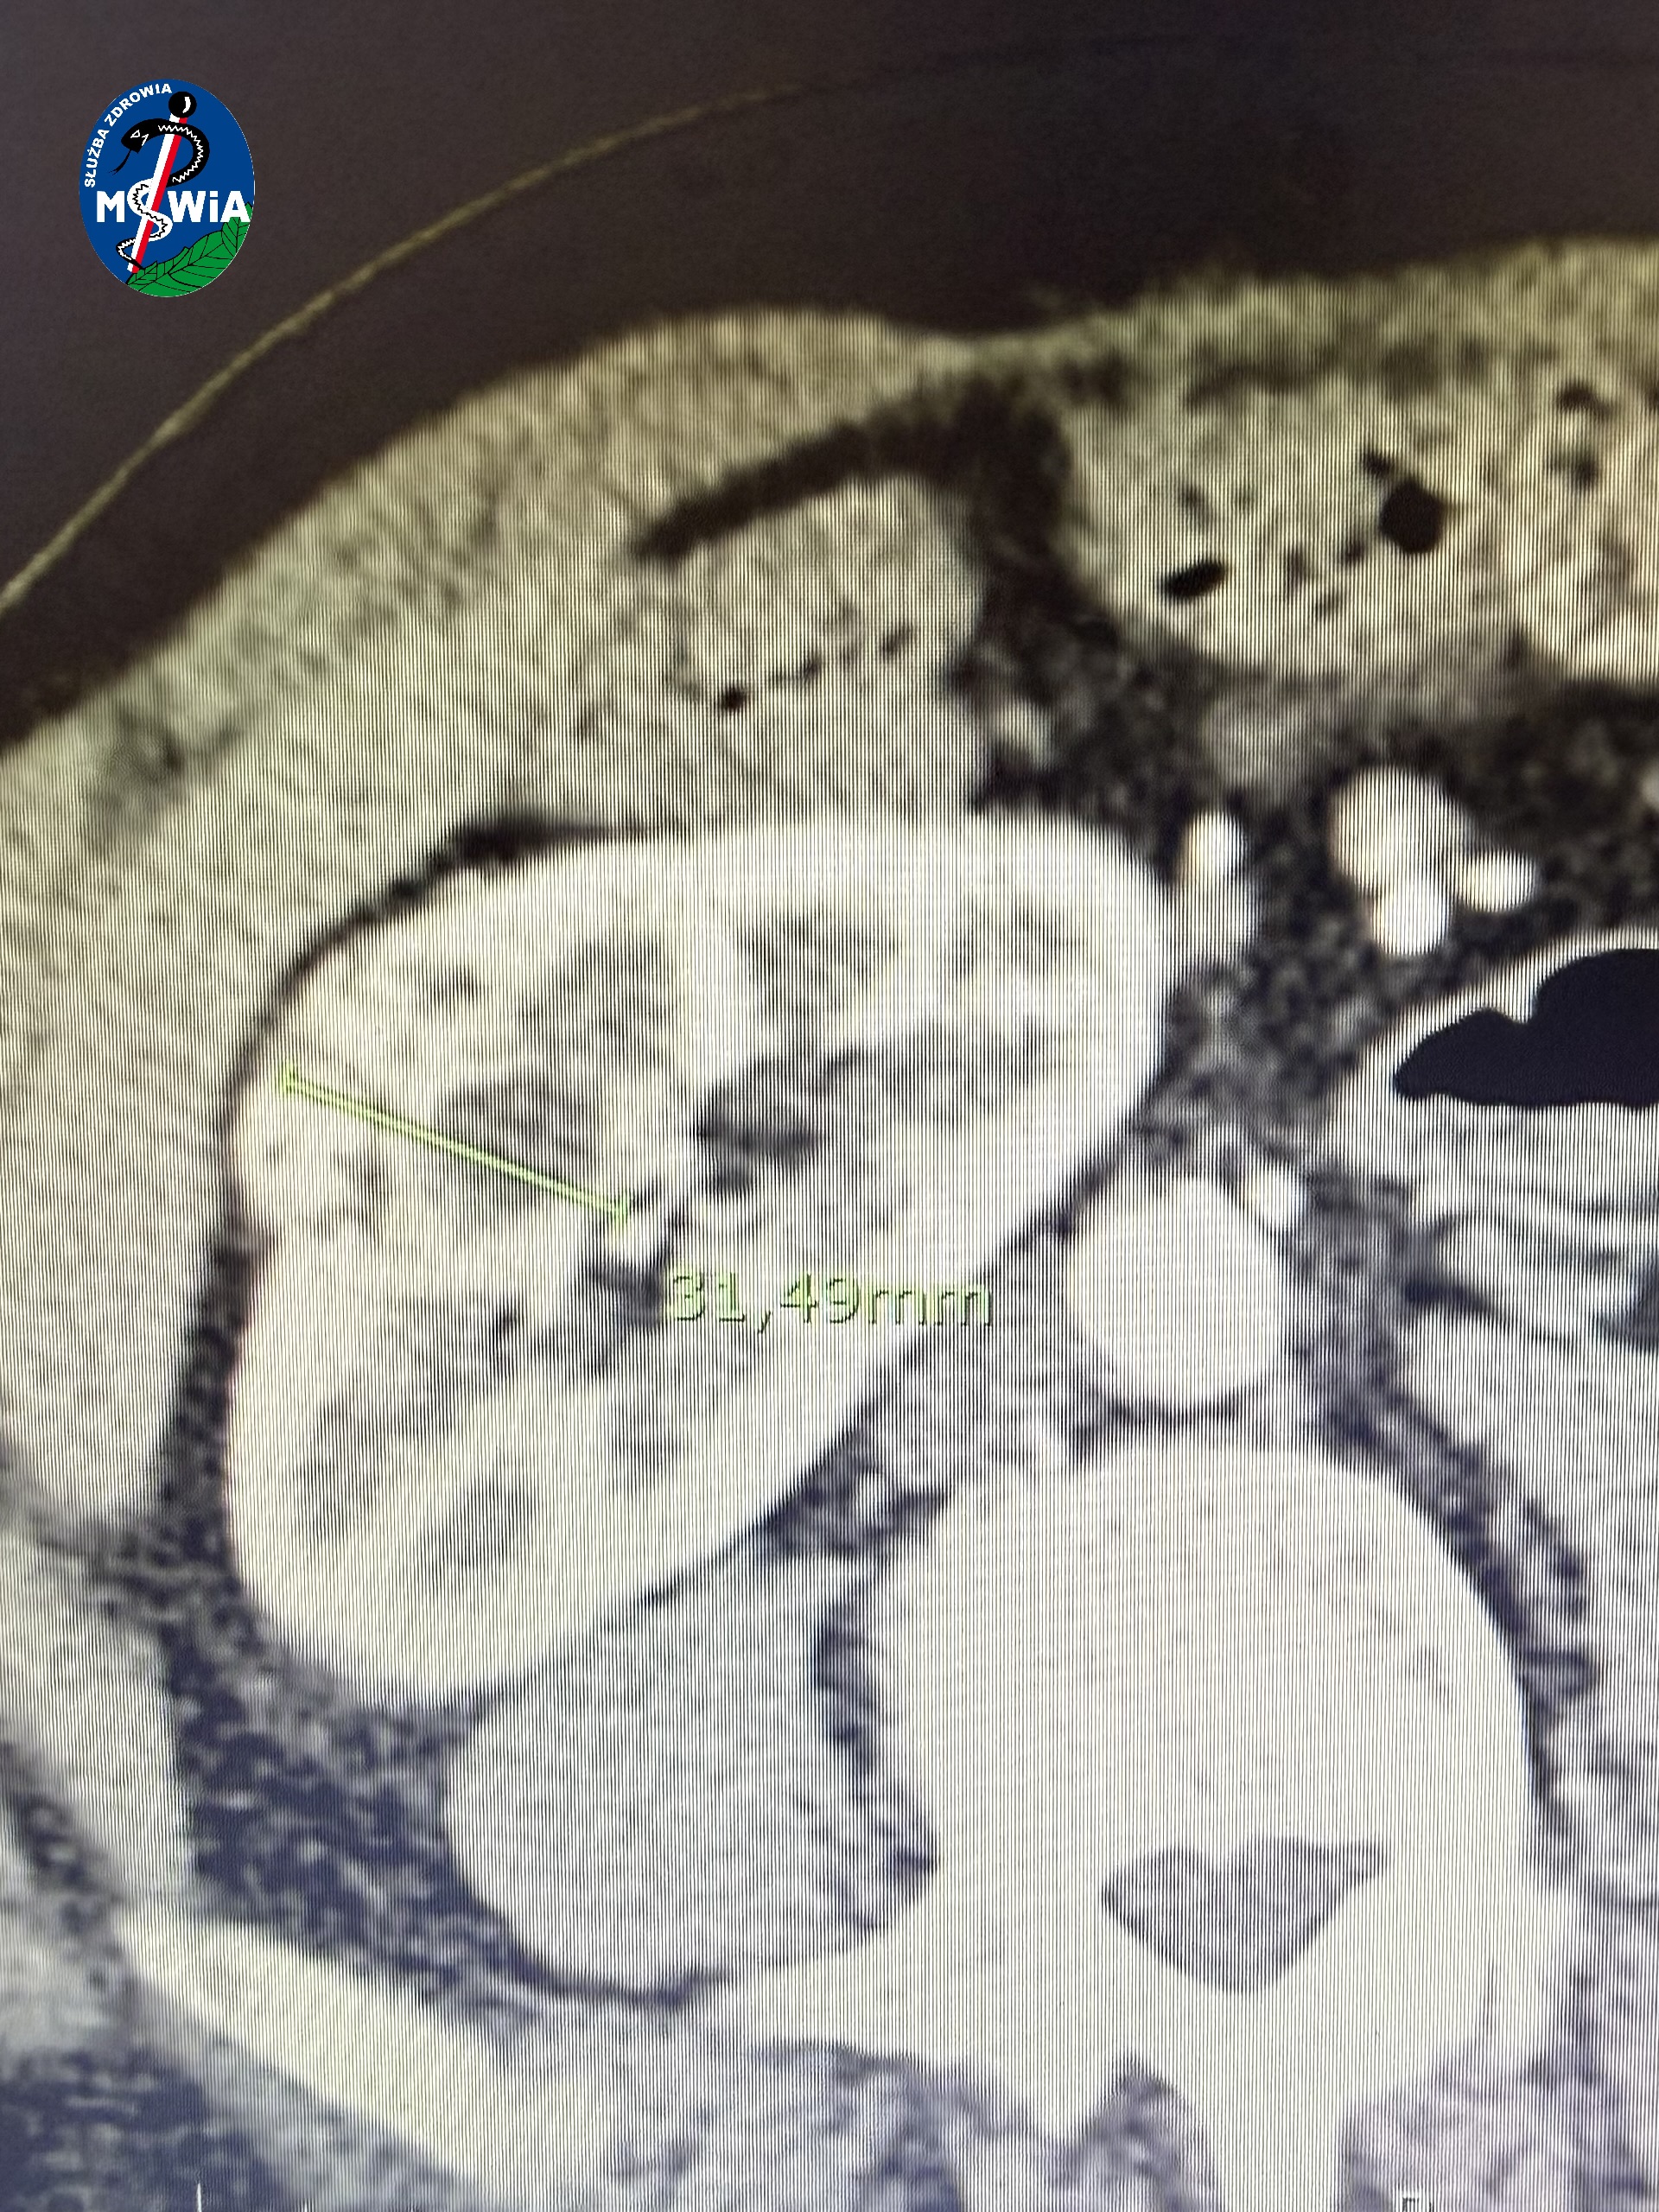

7 listopada w Szpitalu Klinicznym MSWiA w Olsztynie zespół w składzie: dr n. med. Maciej Przudzik (operator), dr Ignacy Bojanowski (asysta), Karolina Lis (pielęgniarka operacyjna), Małgorzata Kłos (pielęgniarka operacyjna), dr Tomasz Gąsiorek (anestezjolog), Elżbieta Borkowska (pielęgniarka anestezjologiczna) przeprowadził pierwszą w regionie operację częściowej resekcji guza nerki w asyście robota (RAPN). Guz nerki był trudno położony, a pacjent był już po wcześniejszych operacjach w obrębie jamy brzusznej i bardzo chciał uniknąć usunięcia nerki. Guz usunięto małoinwazyjnie, precyzyjnie z marginesem zdrowej tkanki.